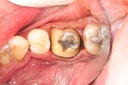

Alan Chinn #28 caries removal